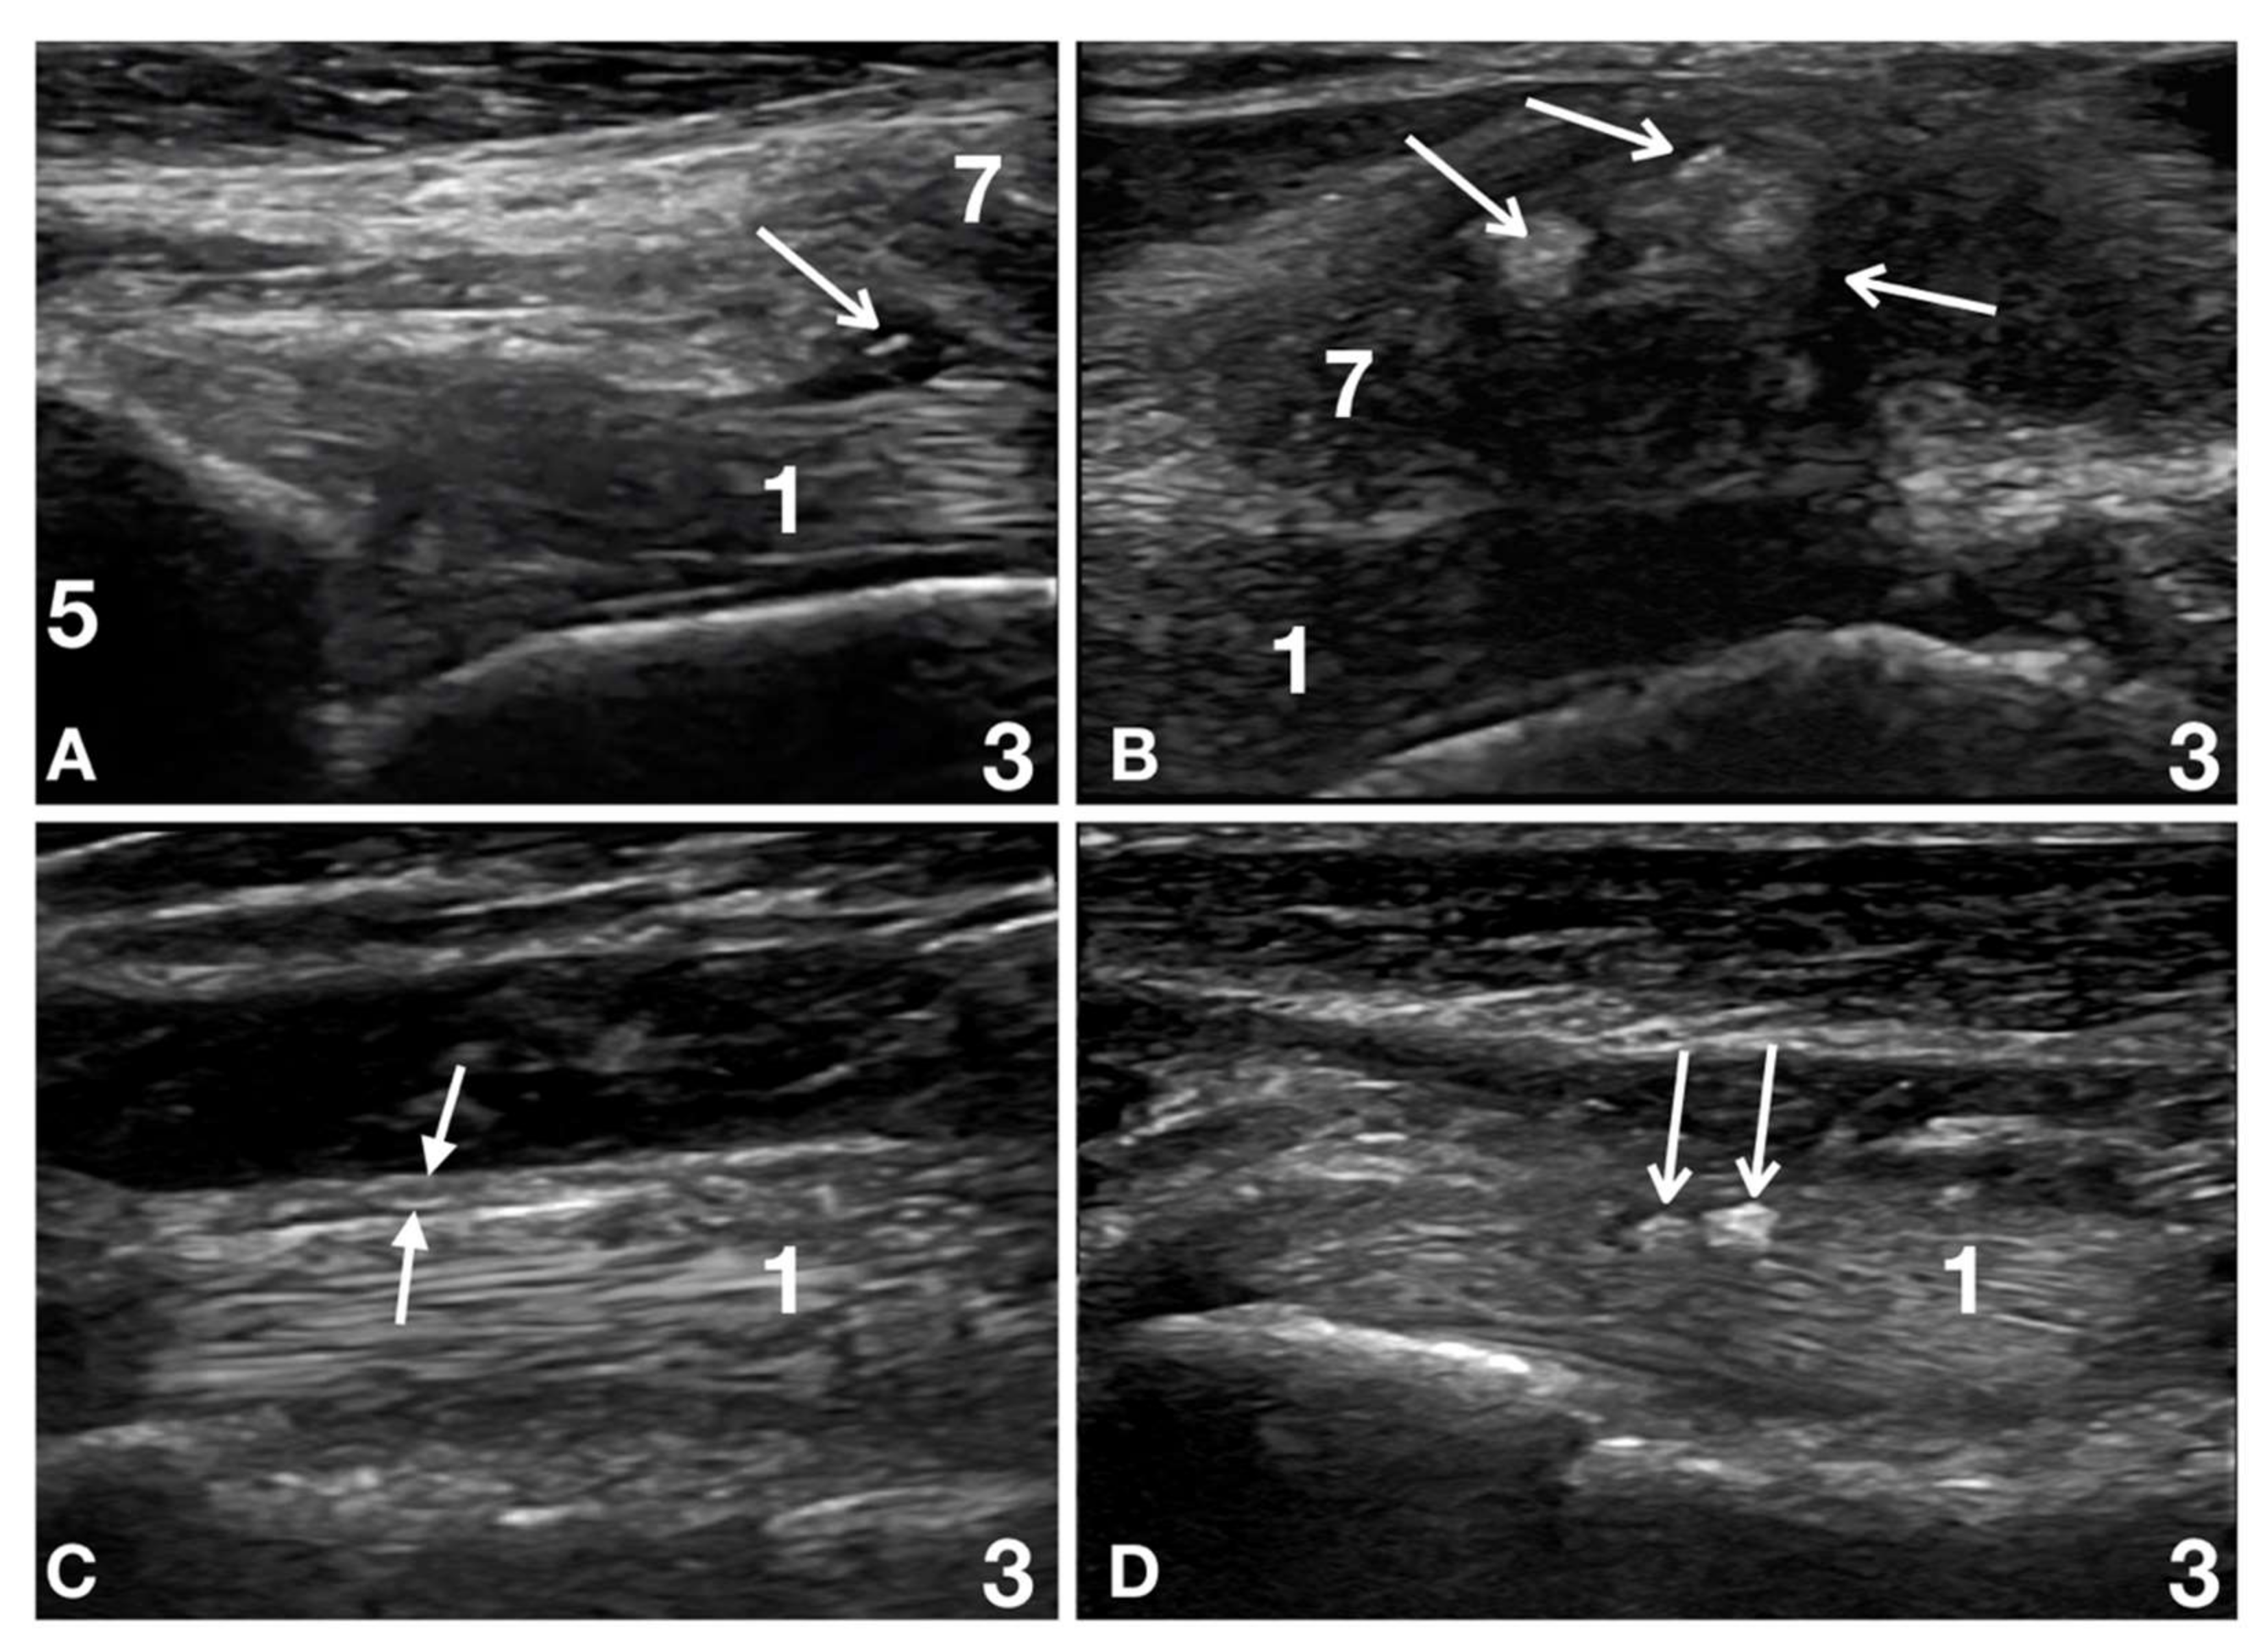

Thirteen patients (13/32; 41%) had biceps tendon lesions associated with supraspinatus tendon lesions, and adhesions between those two structures were present in seven of the thirteen dogs (7/13; 54%) (Figure 2).

Figure 2.

Images of the left shoulder at the level of the biceps tendon origin and supraspinatus humeral insertion of patient number 14 at Time 0, Time 2, Time 4 and Time 6. (A) Time 0: the supraglenoid tubercle (5) with the origin of the biceps tendon (1) is seen. There is no clear definition between the biceps tendon (1), the joint capsule (between arrows in panels c and d), and the tendinous (6) and fibro-cartilaginous (7) (visible in panel b, c and d) portions of the supraspinatus tendon. At dynamic examination, there were no relative motions between the biceps and the supraspinatus tendons. The joint capsule was not identified between these two structures. This condition is called adhesive capsulitis [20]. (B) Time 2: There is a better definition between the biceps tendon (1) and the tendinous (6) and fibrocartilaginous (7) portions of the supraspinatus tendon; however, these structures show adhesions at dynamic examination. The joint capsule (between the arrows in panels C,D) is not identified. The adhesive capsulitis is still present. (C) Time 4: There is a better definition between the biceps tendon (1) and the tendinous (6) and fibrocartilaginous (7) portions of the supraspinatus tendon, and no adhesion is seen at dynamic examination. The joint capsule (between the arrows) is thickened and irregular but is identified as an independent structure. The adhesive capsulitis is resolved. (D) Time 6: the biceps tendon (1) is clearly defined with a richer fibrillar pattern. The joint capsule (between the arrows) is better defined, less thickened and more regular than before. No interference is seen at dynamic examination between the joint capsule and the biceps tendon (1). No interference is visible between the joint capsule and the tendinous (6) and fibrocartilaginous (7) portions of the supraspinatus tendon.